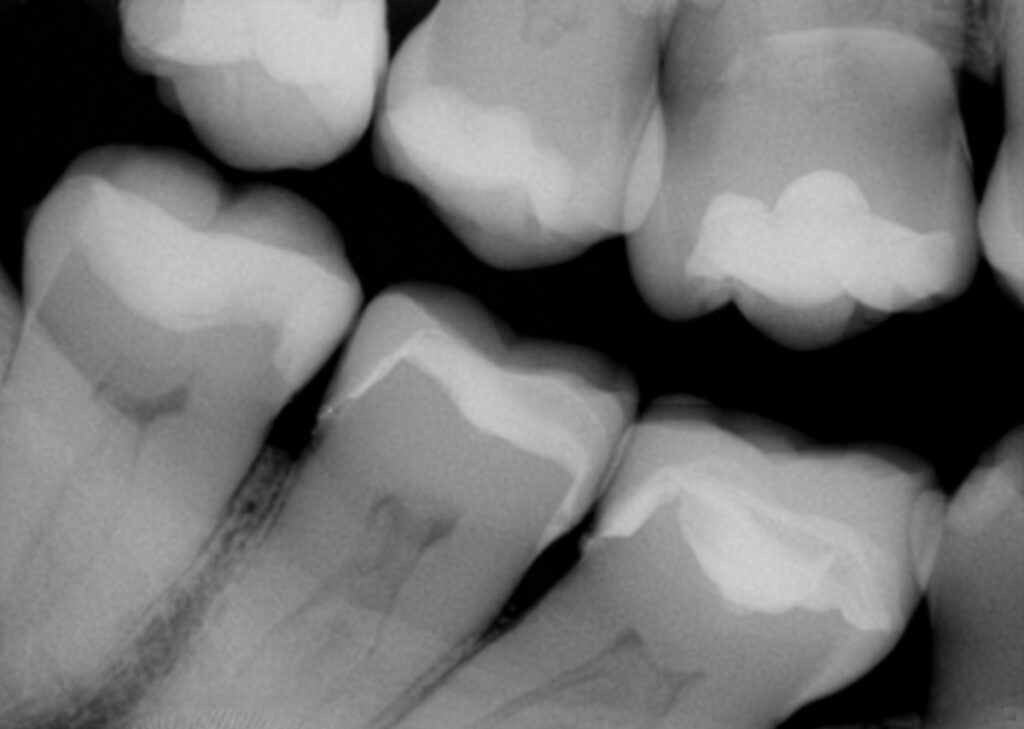

From www.clarencetam.co.nz

Vertical Hairline Fractures on an amalgam filled wisdom tooth Hairline Fracture Tooth Symptoms If these cracks don’t affect appearance and don’t produce pain, your doctor may advise leaving them alone. Sensitivity to hot, cold, or. Not every hairline tooth fracture will have symptoms. However, experiencing any of the following could be a sign that. Symptoms of a hairline tooth fracture. Chipping, breaking or cracking a tooth is usually not serious. Sensitivity to hot. Hairline Fracture Tooth Symptoms.

Vertical Hairline Fractures on an amalgam filled wisdom tooth Hairline Fracture Tooth Symptoms See a dentist if you or your child has: Give your dentist a call if you have symptoms of a cracked tooth, like a toothache, or if your tooth hurts when you bite down on it while chewing. The symptoms of a hairline fracture in a tooth can vary depending on the severity of the crack and its location. A. Hairline Fracture Tooth Symptoms.